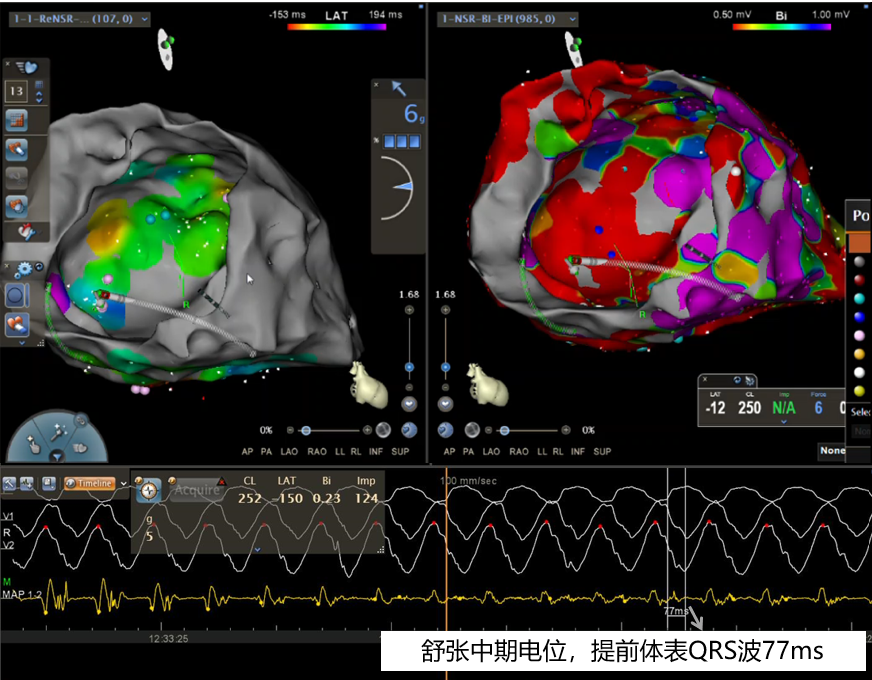

图片

心外膜基质标测:青点和蓝点为不同形态LAVA电位

激动标测:室速发作,大头电极记录到舒张中期电位,提前体表QRS波77ms,考虑该处可能为室速发作时的关键峡部,于此处放电,室速终止